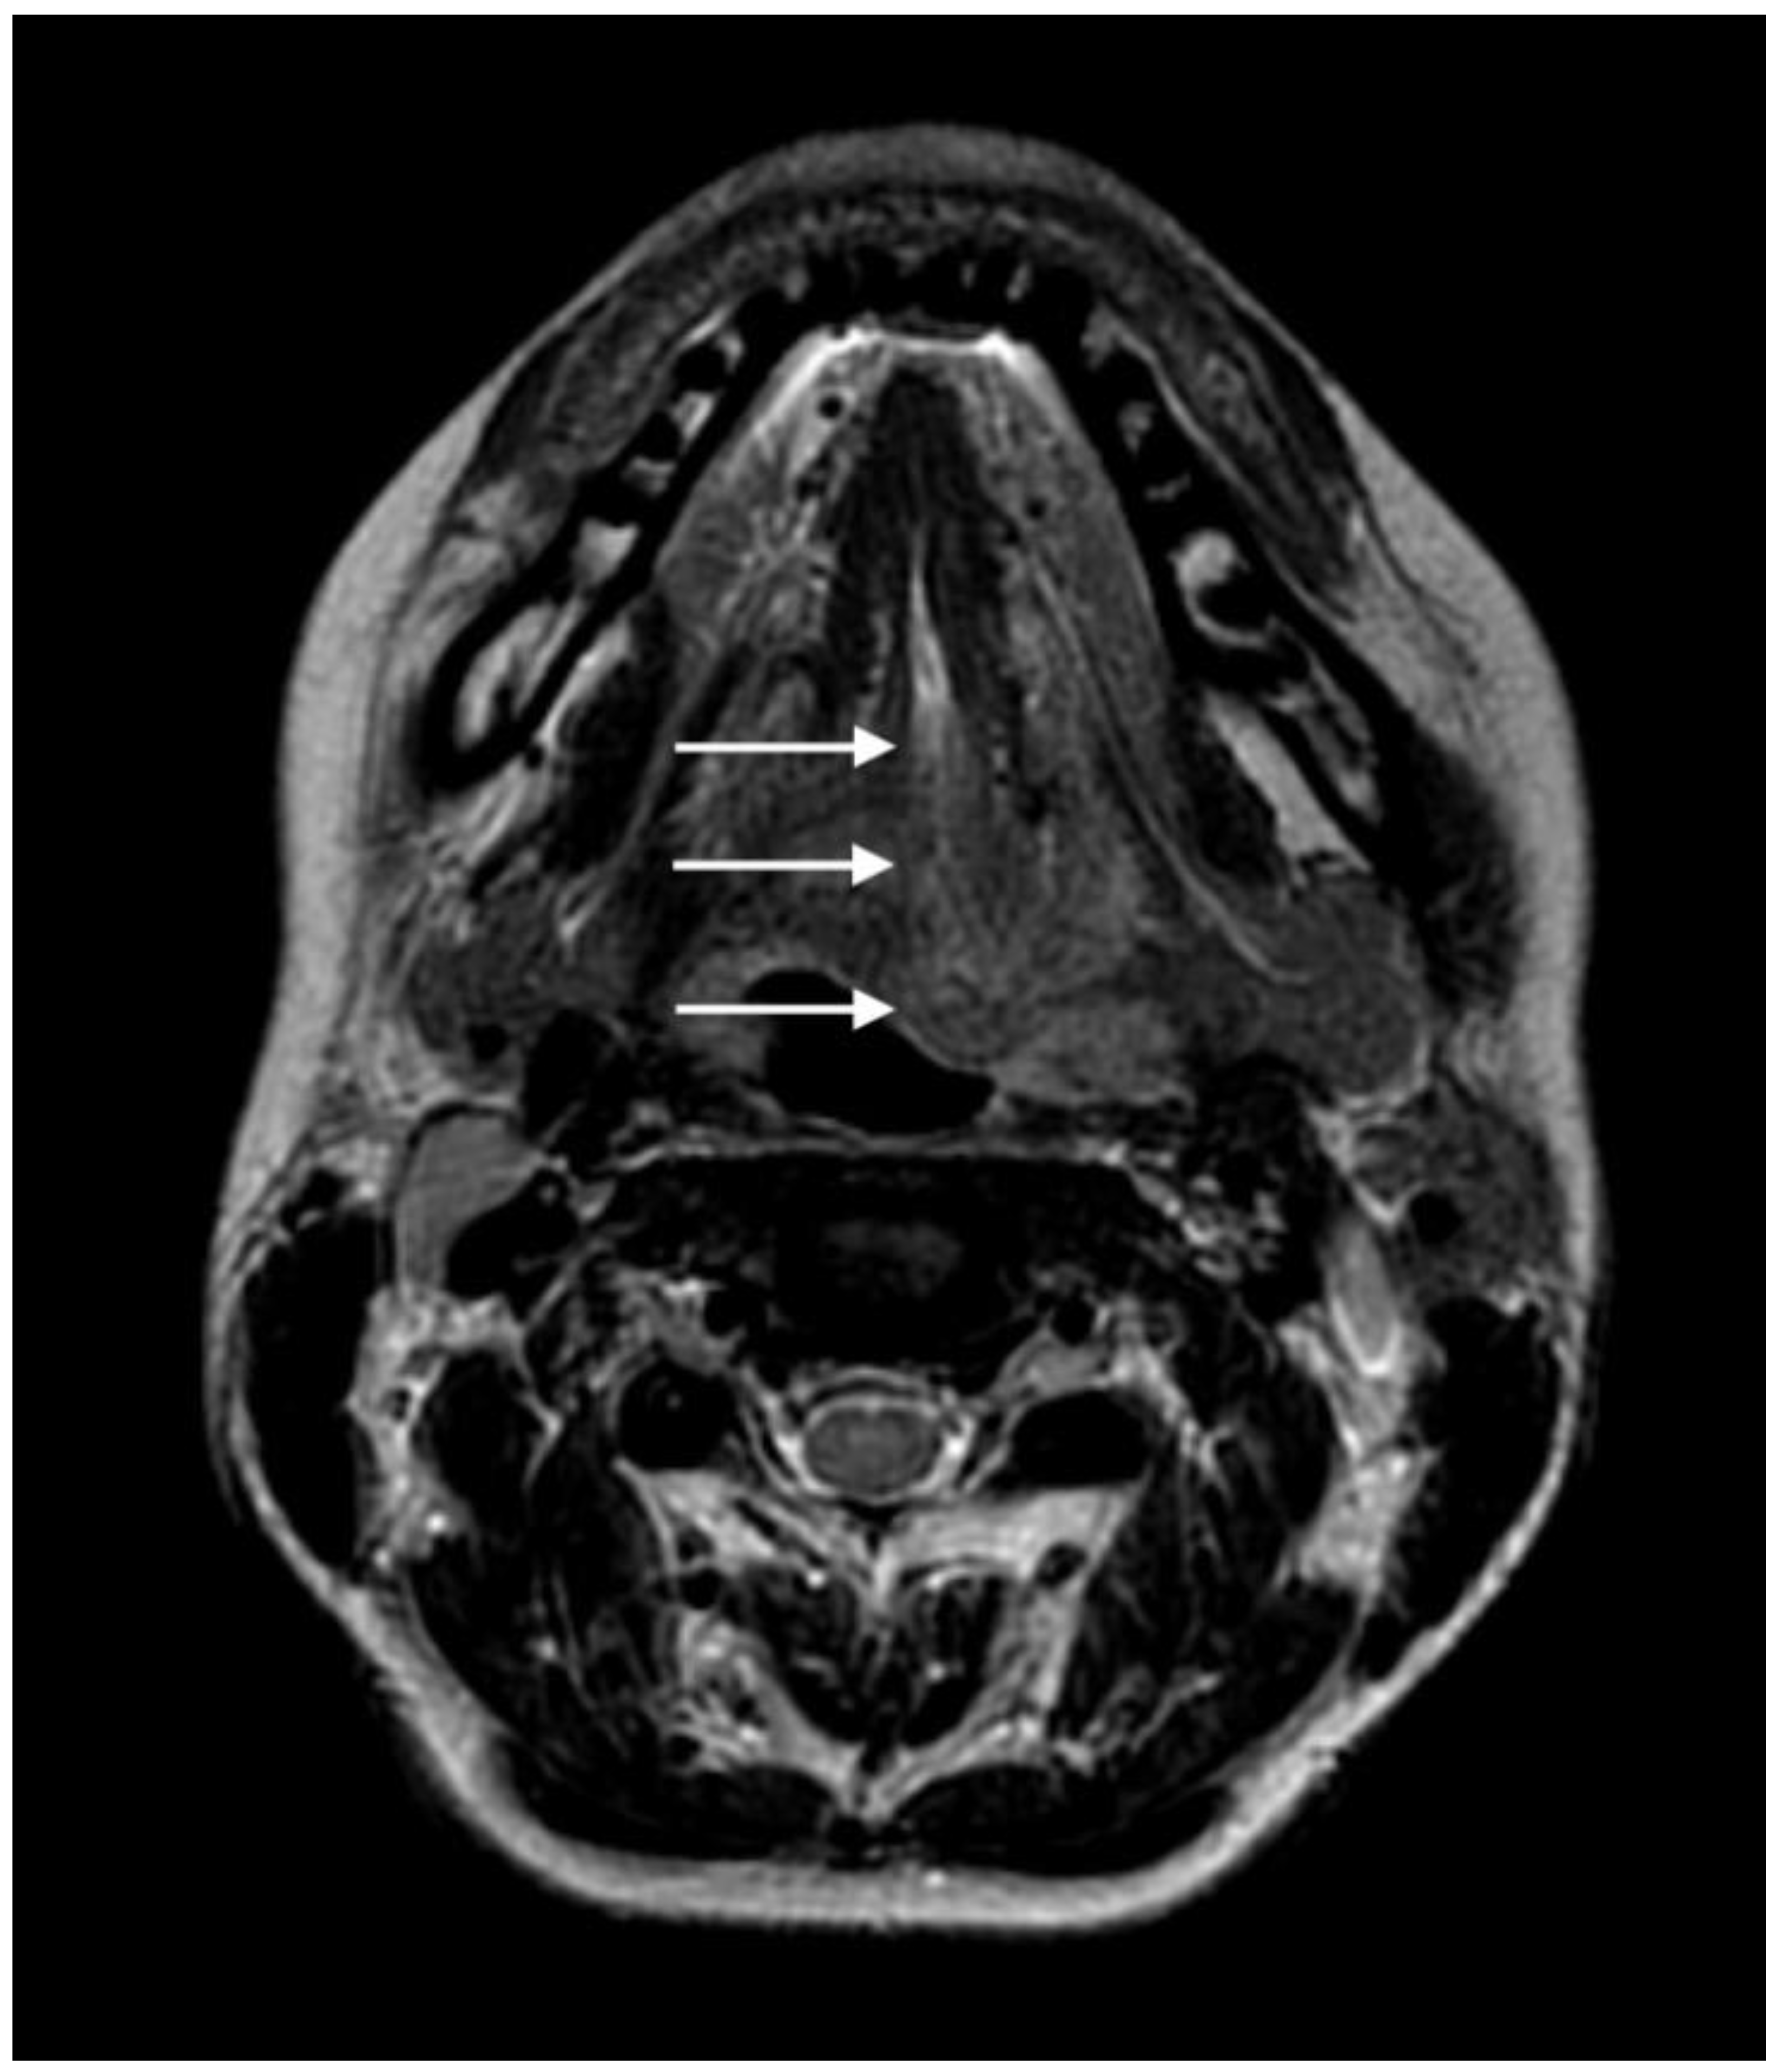

2. Case Presentation

2.2. Diagnosis